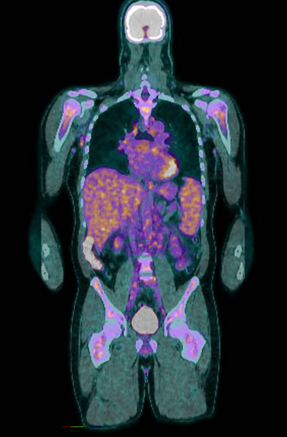

A positron emission tomography scan showed innumerable mildly to moderately fludeoxyglucose (FDG)‐avid enlarged and non‐enlarged lymph nodes above and below the diaphragm, and increased splenic and bone marrow activity (Box 3). Biopsy samples were taken from the most FDG‐avid axillary and mediastinal lymph nodes, but were non‐diagnostic. The results from one biopsy showed non‐caseating granulomas; however, results from the second biopsy did not. An excisional lymph node biopsy was subsequently taken, with the results meeting histopathologic criteria for Castleman disease (Box 4). These criteria included depleted germinal centres, concentric rimming of small B lymphocytes in a “onion skin” appearance, and vascularity with vessels extending into the germinal centre.1